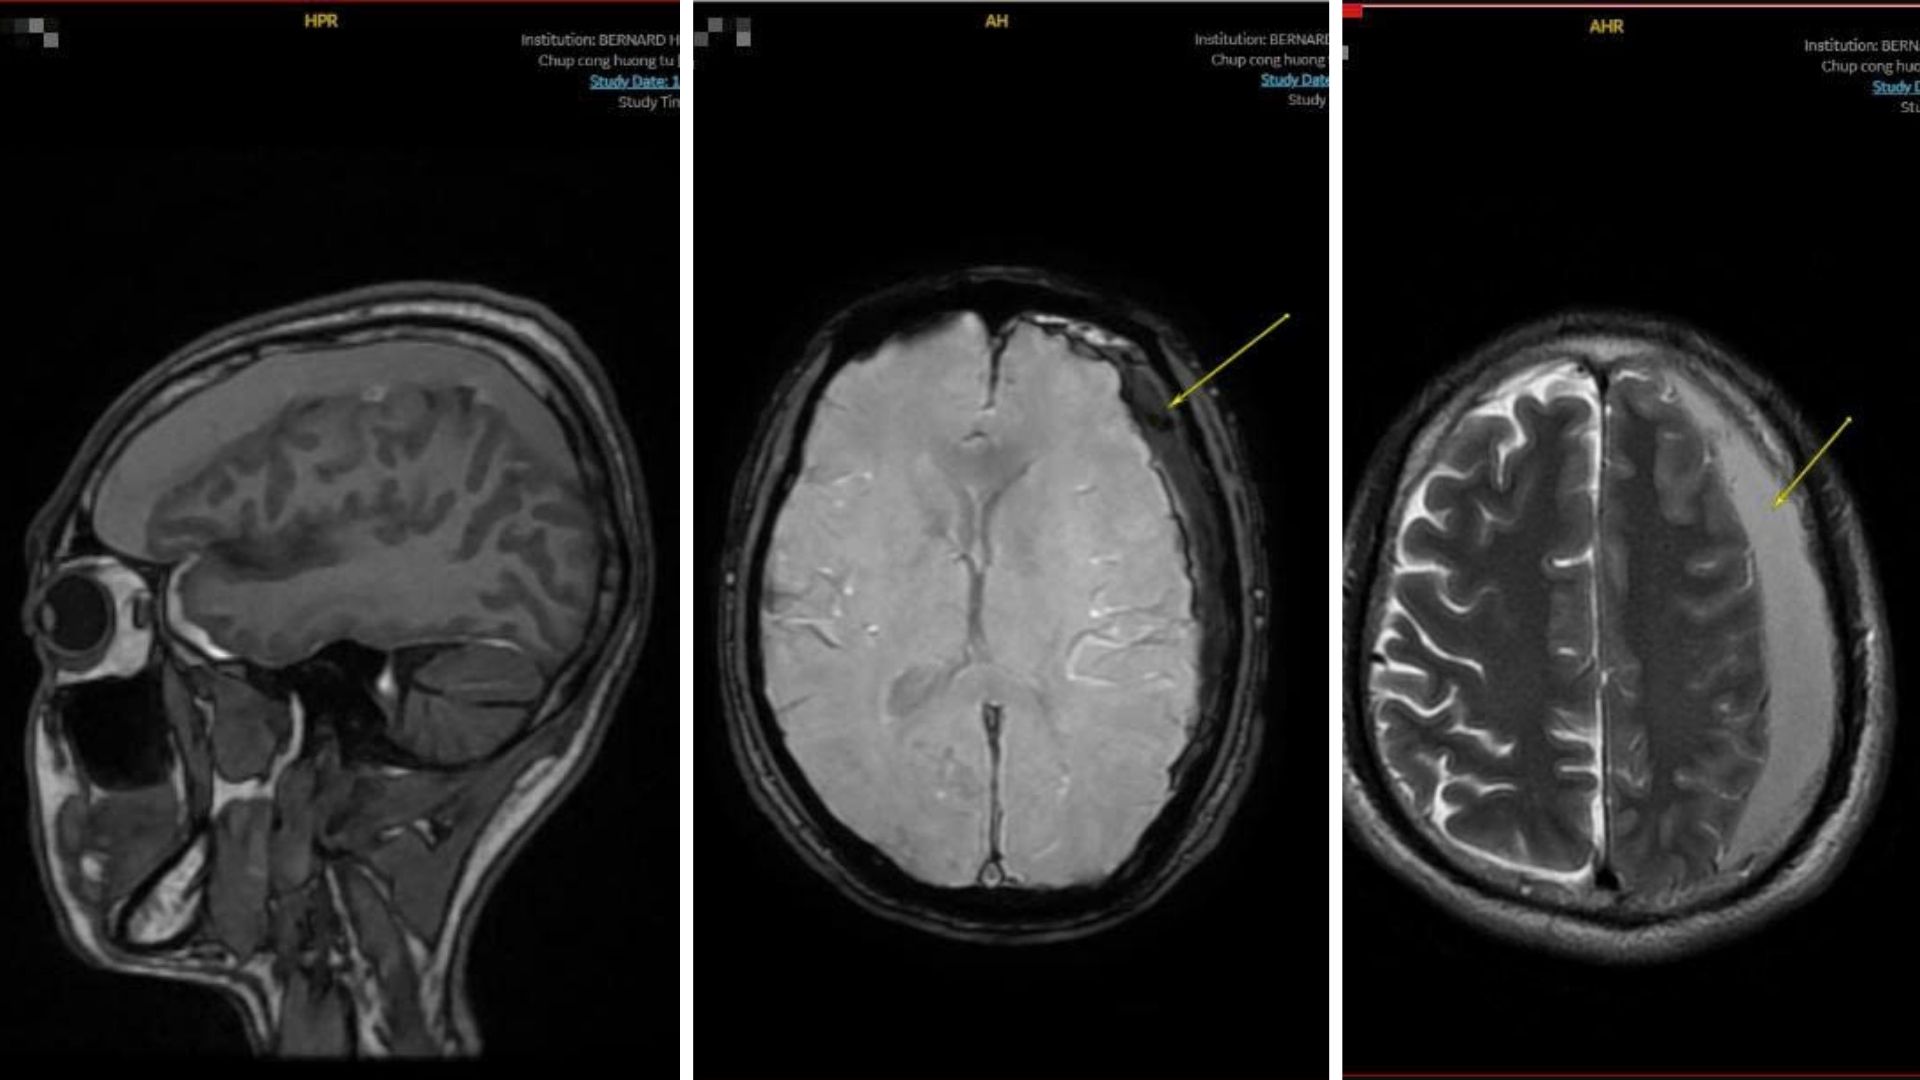

Kết quả MRI ghi nhận đồng thời nhiều dấu hiệu nguy hiểm. Bệnh nhân có tụ máu dưới màng cứng bán cầu não trái, dọc liềm não và lều tiểu não trái, bề dày khối máu tụ dmax khoảng 18mm.

Khối máu tụ đã ép não thất bên trái, khiến đường giữa lệch nhẹ sang phải. Dấu hiệu của khối máu tụ nhiều giai đoạn (cấp - bán cấp), cho thấy tình trạng đã tồn tại một thời gian dài.

Khi có kết quả MRI, Bernard Healthcare kích hoạt quy trình xử trí ca nguy cơ cao. Bác sĩ chẩn đoán hình ảnh mô tả chi tiết vị trí, giai đoạn của máu tụ, mức độ đè ép nhu mô và lệch đường giữa, những thông số quyết định người bệnh cần can thiệp ngoại khoa hay theo dõi.